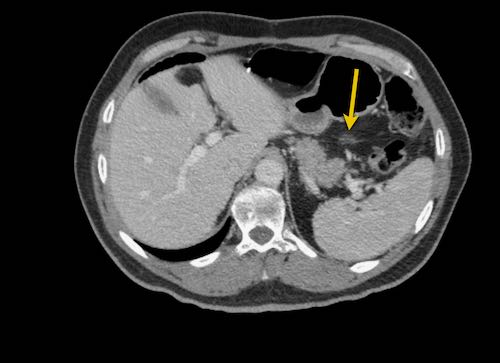

Hình ảnh

Hình ảnh CT của một bệnh nhân ung thư phúc mạc.

Một lượng nhỏ dịch cổ trướng hiện diện ở góc phần tư trước bên phải.

Các đường dày dạng nốt vuông góc với thành ruột được ghi nhận.

Hình ảnh này đại diện cho tổn thương xâm lấn mạc treo ruột lan rộng (mũi tên).